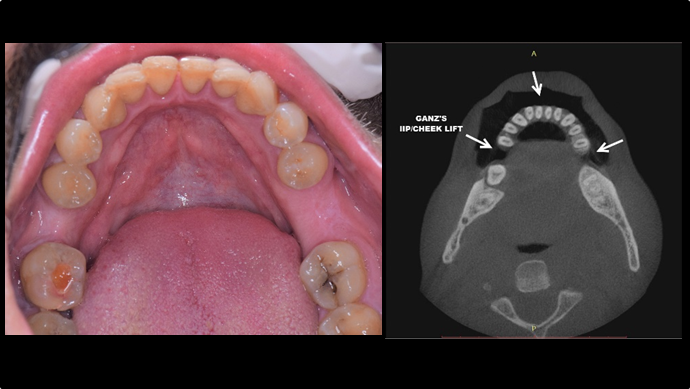

“Automated customized drilling protocols for optimum implant stability/ ONE-DAY implants ”

Clinical case: : Immediate loading of lower molars using R2Gate prefabricated 3D-printed provisional restoration

- Courtesy of Dr. Sam Omar, Egypt -

Dr.Sam Omar, immediate loading, digital guided surgery, digital ONE-DAY implant, maxillary anterior, #21, guided surgery, immediate loading, AnyRidge, R2GATE, Mega ISQ, MEG Torq, R2GATE Full Surgical Kit

implant system, R2GATE Guide, R2GATE surgical kit (AnyRidge), Mega ISQ